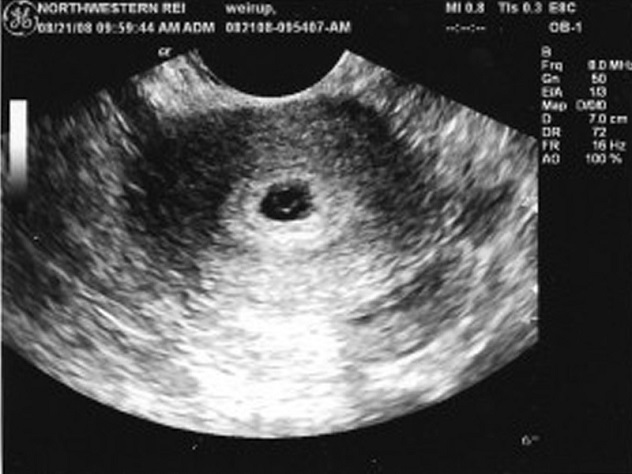

- Плодное яйцо является первым признаком нормального течения беременности. Его можно увидеть на ультразвуковом исследовании уже через две недели после задержки менструации, обычно на 3-4 неделе. Эмбрион становится видимым только на пятой неделе беременности. Если на пятой неделе врач не обнаруживает эмбриона в плодном яйце, то УЗИ повторяют через пару недель.

Плодное яйцо, диаметр которого в первые дни беременности довольно небольшой, можно заметить уже через две-три недели после задержки менструации. Обычно сформированная структура располагается в верхней части маточной полости, имеет темный (серый) оттенок и округлую или овальную форму. На этом этапе эмбрион еще очень мал, поэтому его невозможно обнаружить при ультразвуковом исследовании.

При первом ультразвуковом исследовании, которое проводится при задержке менструации для подтверждения маточной беременности, можно увидеть плодное яйцо. В этот момент врач сообщает вам радостную новость о том, что вы скоро станете мамой. На экране вы увидите плодное яйцо — небольшое овальное образование. На ранних сроках эмбрион, который будет развиваться внутри плодного яйца, еще не виден, но вскоре он подрастет и станет заметным.

Пустое плодное яйцо — это яйцо без эмбриона, что указывает на отсутствие развития беременности. Обычно эмбрион становится видимым уже на пятой неделе, однако бывают случаи, когда на этом сроке его не удается обнаружить, и в таких ситуациях назначается повторное УЗИ. Часто повторное исследование показывает как эмбрион, так и сердцебиение. Если после шести-семи недель эмбрион не виден, это может свидетельствовать о том, что беременность не развивается.